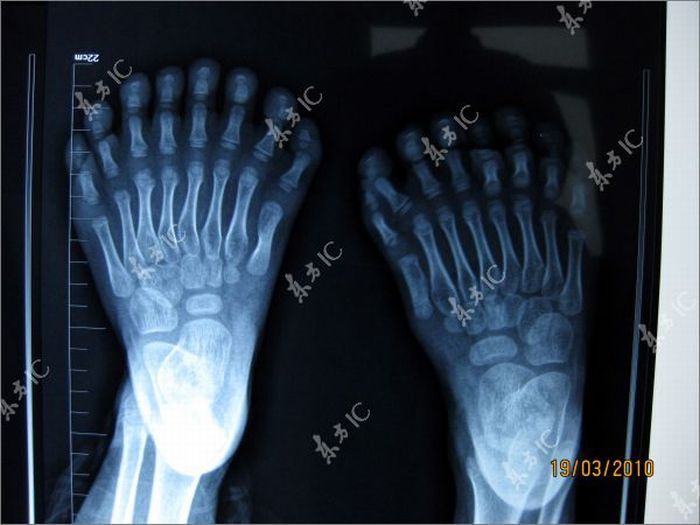

Chinese boy with 30 fingers and toes

Polydactyly or polydactylism (from Ancient Greek πολύς (polus) "many" + δάκτυλος (daktulos) "finger"), also known as hyperdactyly, is a congenital physical anomaly in humans having supernumerary fingers or toes. When each hand or foot has six digits, it is sometimes called sexdactyly, hexadactyly, or hexadactylism. Polydactyly can occur by itself, or more commonly, as one feature of a syndrome of congenital anomalies. The condition has an incidence of 1 in every 1000 live births.